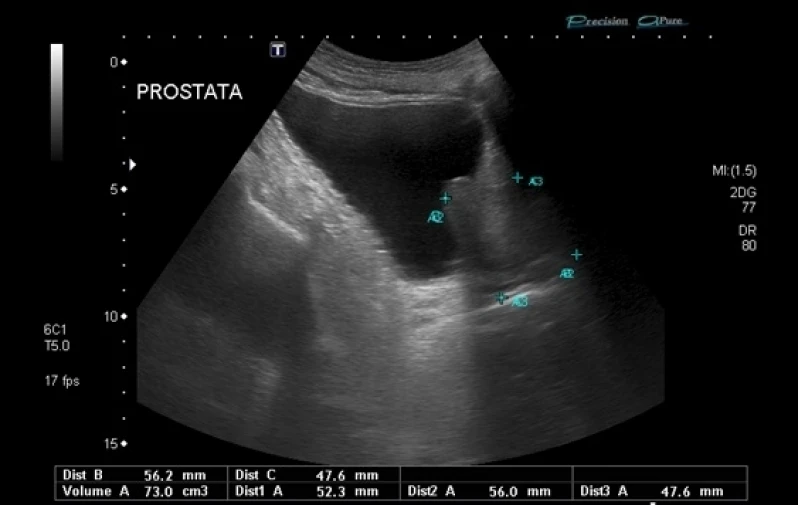

Os urologistas são médicos especializados no diagnóstico e tratamento de doenças do sistema urinário e reprodutor masculino. Eles tratam desde infecções urinárias até câncer de próstata e disfunção erétil. Além disso, os urologistas também realizam cirurgias para correção de problemas como incontinência urinária e obstruções do trato urinário. É importante que homens e mulheres consultem um urologista regularmente para prevenir e tratar possíveis problemas de saúde. Na DK Urologistas, contamos com uma equipe de profissionais altamente capacitados e equipamentos de última geração para oferecer o melhor atendimento aos nossos pacientes. Agende sua consulta conosco e cuide da sua saúde urológica.